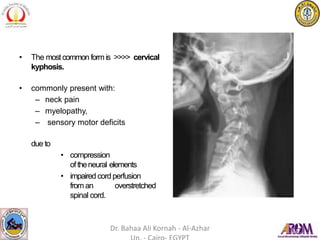

• The mostcommon form is >>>> cervical

kyphosis.

• commonly present with:

– neck pain

– myelopathy,

– sensory motor deficits

due to

• compression

oftheneural elements

• impaired cordperfusion

froman overstretched

spinal cord.